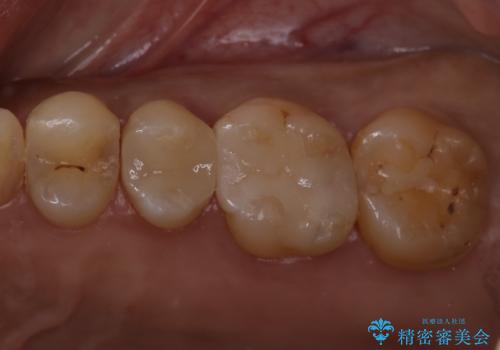

定期検診で虫歯発見。セラミック治療

- 定期検診に通われている患者様で虫歯を発見し患者様に話をしたら、治療を進めていきたいとのことだったので治療を行いました。

まずは虫歯をしっかりと取る事が大切です。

虫歯をとった後は、削った形に型を取る事で隙間なく歯にあった被せ物ができてきます。